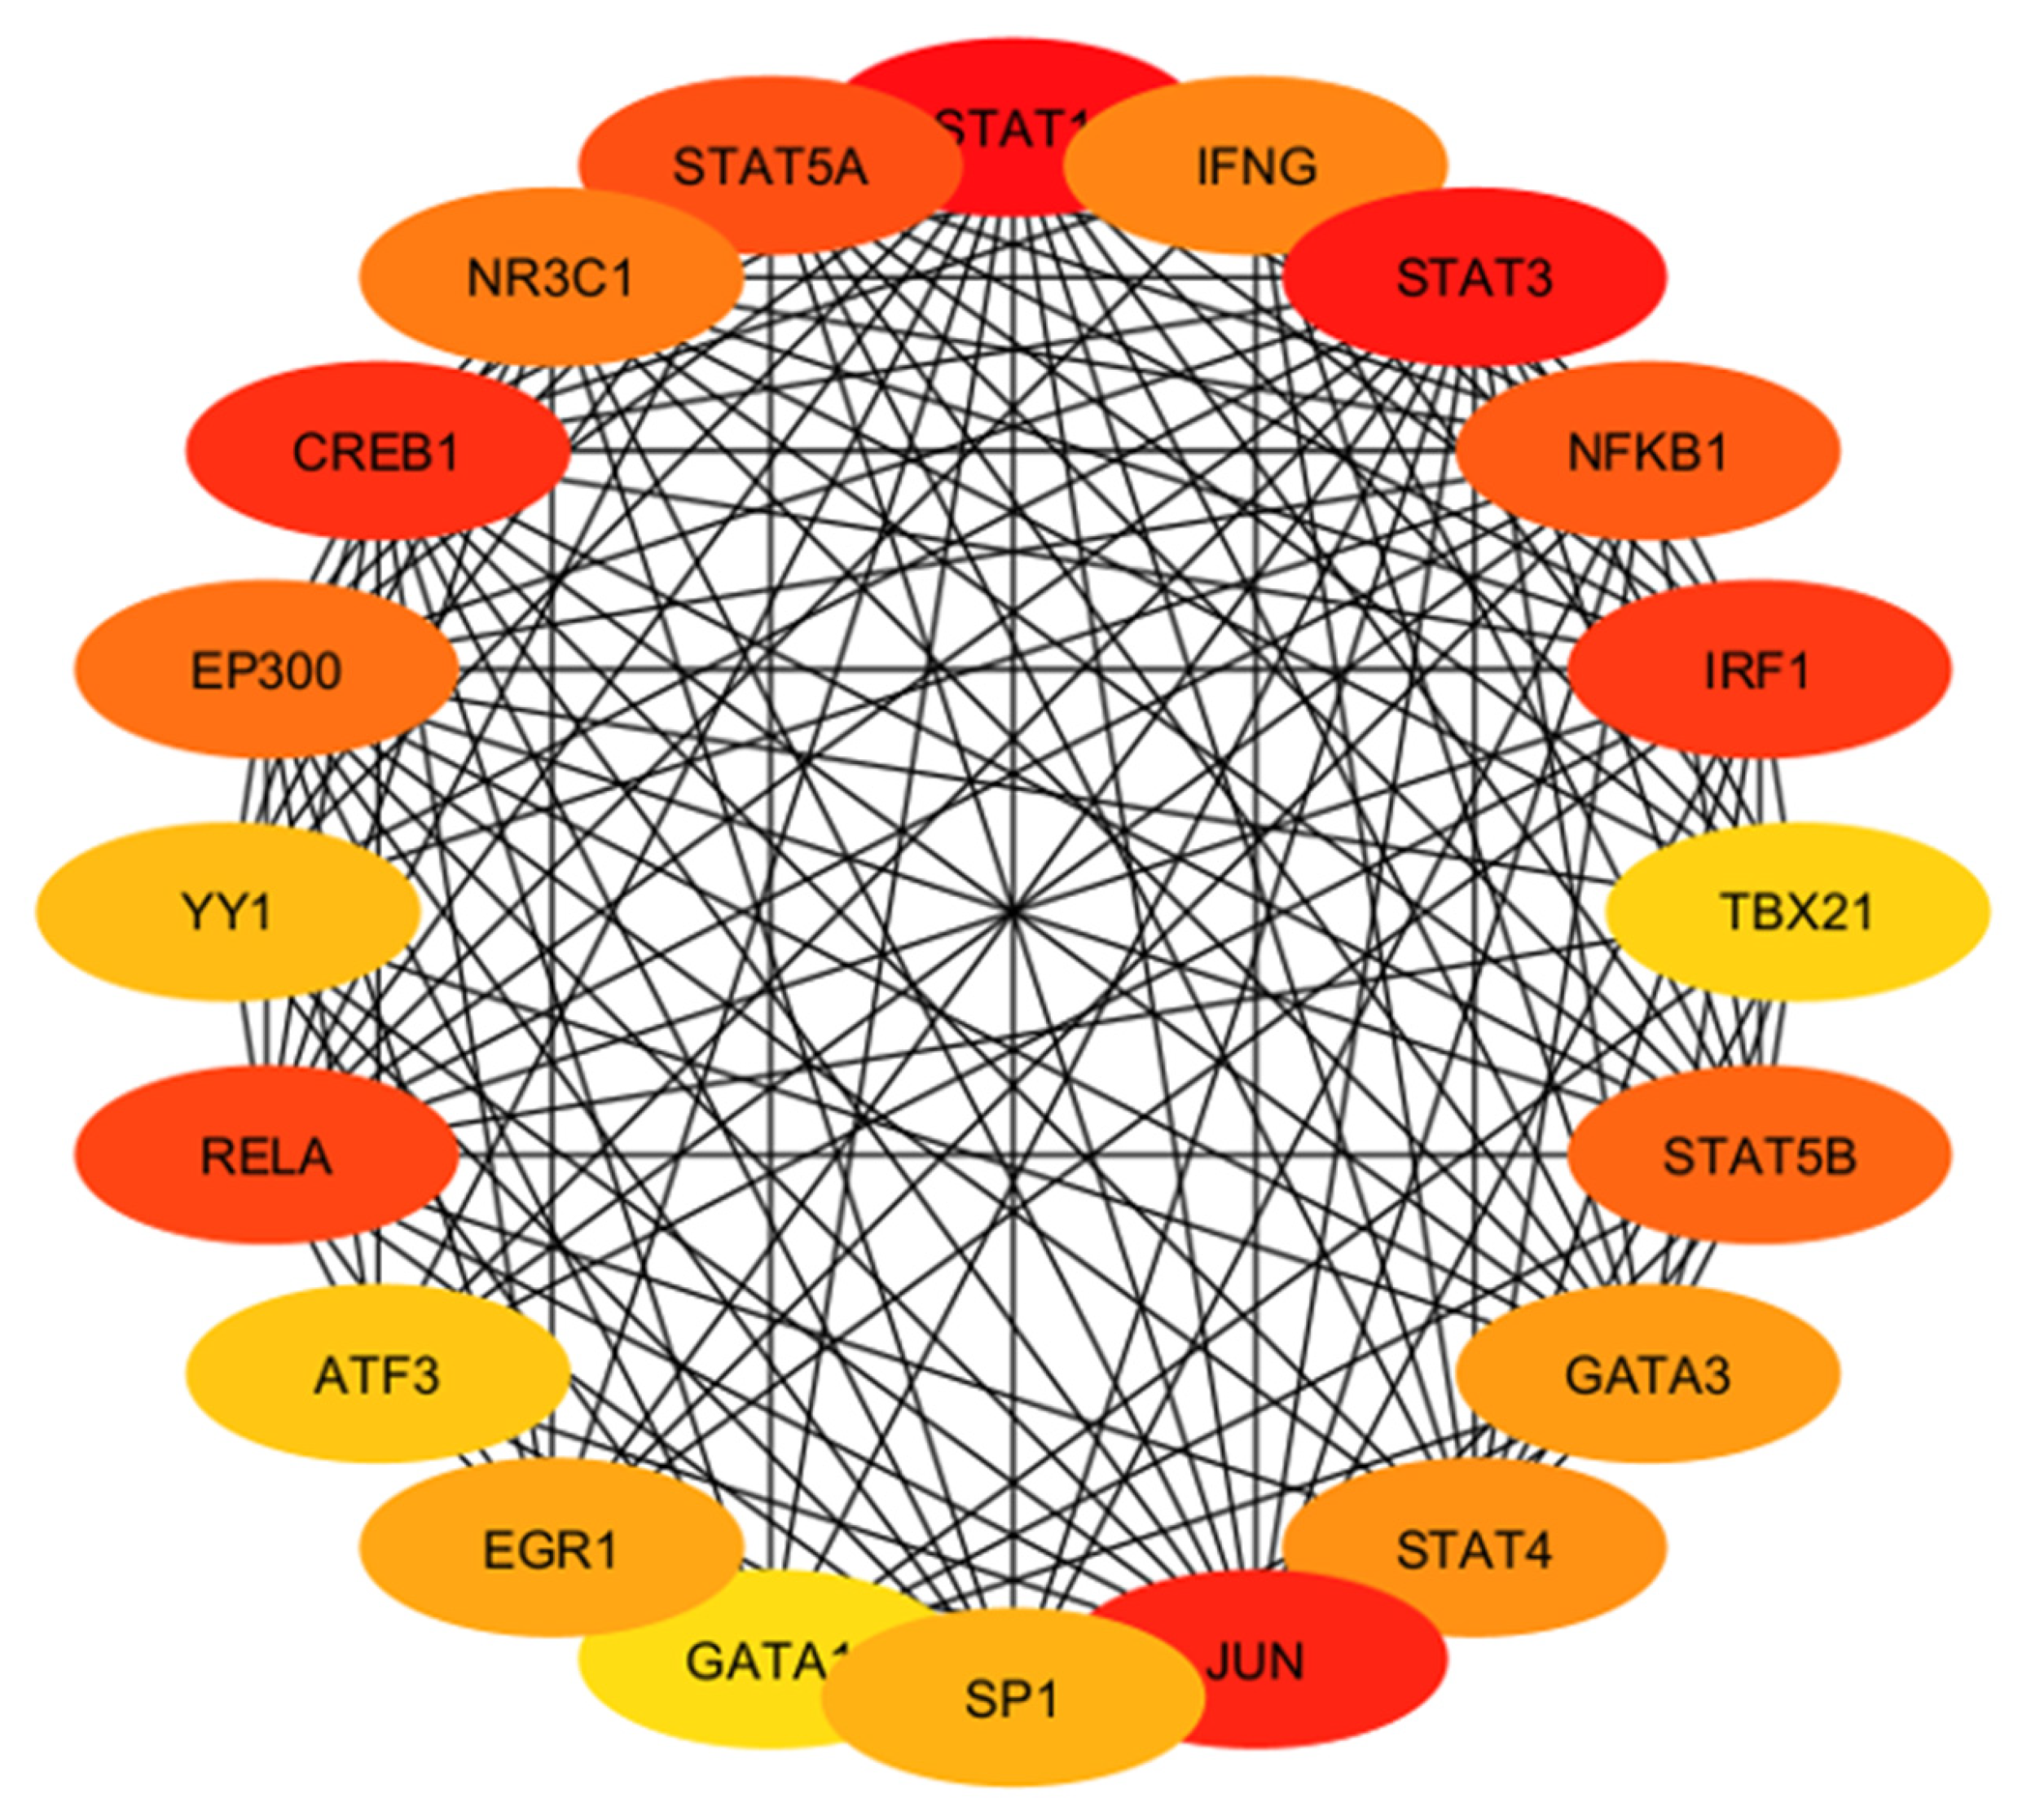

2.4.4. Identification and Analysis of Hub Gene

2.4.5. Gene Ontology and Functional Annotation Analysis of Hub Genes

4.5. Hub Genes with Diagnostic and Therapeutic Perspectives

| Hub Gene | Tissue Expression | Single-Cell Normalized Expression (nTPM) | Associated Genes | Functions |

|---|---|---|---|---|

| IFNG | Ovary, uterus placenta | Endometrium 0.9 | IFNGR1, IFNGR2, FOXP3, RUNX1, TRIM28 | Regulates cell differentiation, activation, expansion, homeostasis, and survival |

| STAT3 | Ovary, uterus placenta | Cyto 27.3; Syncytio: 35.9; extravillous: 49.3; Endometrium 194.6 | BMX, EGFR, JK1, MAPK1, PIAS3 | Controls cell proliferation, migration, apoptosis |

| NFKB1 | Ovary, uterus placenta | Cyto: 15.2; Syncytio:13.5; extravillous: 17.3; Endometrium 60.4 | NFKB1A, RELA, CHUK, IFBKB, RELB | Regulate genes |

| IRF1 | Ovary, uterus placenta | Cyto: 25.0; Syncytio: 9.4; extravillous: 46.9; Endometrium 179.7 | IRF8, STUB1, STAT1, EP300, KAT2B | Regulate innate and adaptive immune responses |

| TBX21 | Ovary, uterus placenta | - | CREBBP, EP300, GATA3, SP1, UBC, TBX21 | Regulates development of naive T lymphocytes |

| STAT5B | Ovary, uterus placenta | Cyto: 8.0; Syncytio: 13.8; extravillous: 5.9; Endometrium 20.5 | EGFR, INSR, JAK1, JAK2, JAK3 | Regulates formation of tissues and organs; maintains immune homeostasis |

| GATA3 | Ovary, uterus placenta | Cyto: 329.4; Syncytio: 1237.7; extravillous: 843.6; Endometrium 0.4 | HDAC1, HDAC2, HDAC3, LMO1, TAL1 | Regulates cell maturation with proliferation arrest and cell survival |

| STAT4 | Ovary, uterus placenta | Cyto: 0.4; Syncytio: 0.4; extravillous: 3.4; Endometrium 0.4 | JUN, IL12RB2, PIAS2, STAT1, ZNF467 | Regulates innate and adaptive immune responses |

| JUN | Ovary, uterus placenta | Cyto: 666.6; Syncytio: 405.9; extravillous: 61.9; Endometrium 2873.0 | ATF2, FOS, MAPK8, MAPK9, MAPK10 | Cell proliferation, apoptosis and survival, and tissue morphogenesis |

| SP1 | Ovary, uterus placenta | Cyto: 16.3; Syncytio: 22.4; extravillous: 17.0; Endometrium 22.3 | EP300, ESR1, HDAC1, HDAC2, TP53 | Regulates cell cycle, hormonal activation, apoptosis, and angiogenesis |

| GATA1 | Ovary, uterus placenta | - | BRD3, FLJI1, LMO2, TAL1, ZFPM1 | Regulates development of multipotential progenitors and hematopoietic stem cells |

| EGR1 | Ovary, uterus placenta | Cyto: 154.9; Syncytio: 165.7; extravillous: 106.1; Endometrium 783.3 | EP300, JUNDB, JUNDD, NAB1, TP53 | Regulates attachment and survival of normal cells and induces apoptosis in abnormal cells |

| ATF3 | Ovary, uterus placenta | Cyto: 179.2; Syncytio: 507.9; extravillous: 365.5; Endometrium 321.4 | DDIT3, JUN, JUNB, MDM2, TP53 | Regulates metabolism, immunity, inflammation, cell proliferation, and apoptosis |

| RELA | Ovary, uterus placenta | Cyto: 23.0; Syncytio: 47.7; extravillous: 27.7; Endometrium 24.8 | BRD4, CREBBPEP300, NFKB1, NFKB1A | Regulate genes involved in apoptosis, inflammation, the immune response, and proliferation |

| YY1 | Ovary, uterus placenta | Cyto: 121.3; Syncytio: 177.1; extravillous: 126.4; Endometrium 129.9 | EP300, HDAC2, HDAC3, MBTD1, RUVBL2, | Regulates several biological functions—embryogenesis, differentiation, replication, and cellular proliferation |

| EP300 | Ovary, uterus placenta | Cyto: 17.7; Syncytio: 34.4; extravillous: 19.0; Endometrium 49.1 | CITED2, HIF1A, SMAD3, TCF3, TP53 | Regulates cell growth and division and prompts cell maturation and cells to take specialized functions |

| CREB1 | Ovary, uterus placenta | Cyto: 30.1; Syncytio: 18.7; extravillous: 25.9; Endometrium 37.8 | CREBBP, CRTC2, EP300, RPS6KA5, TP53 | Regulates proliferation, migration, and invasion of cells |

| NR3C1 | Ovary, uterus placenta | Cyto: 48.6; Syncytio: 36.6; extravillous: 44.2; Endometrium 28.5 | HSP90AA1, NCOA1, NCOa2, NCOR, SMARCA4 | Regulates hypothalamic–pituitary–adrenal (HPA) axis by modulating availability of cortisol |

| STAT5A | Ovary, uterus placenta | Cyto: 1.2; Syncytio: 1.3; extravillous: 2.9; Endometrium 5.0 | EGFR, ERBB4, JAK1, JAK2, JAK3 | Relates IL2 signaling, modulates cytokine and growth factor action, modifies chromatin organization |

| STAT1 | Ovary, uterus placenta | Cyto: 13.7; Syncytio: 7.9; extravillous: 60.8; Endometrium 45.2 | CREBBP, JAK2, PIAS1, STAT2, STAT3 | Regulates proinflammation and immune function |